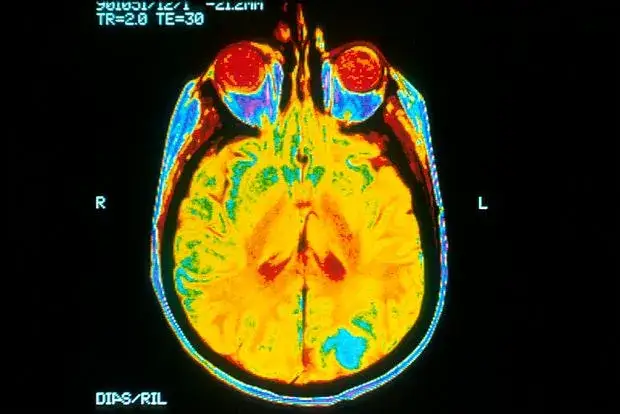

Zmiany strukturalne w mózgu osób z nerwicą

Osoby z nerwicą często wykazują zmiany strukturalne w mózgu, które mogą być zauważalne w badaniach neuroobrazowych. Na przykład, badania wykazały, że osoby z nerwicą mają zmniejszoną objętość hipokampa, obszaru odpowiedzialnego za pamięć i regulację emocji. Tego rodzaju zmiany mogą wpływać na sposób, w jaki jednostki przetwarzają emocje i reagują na stresujące sytuacje.

Inne badania sugerują, że pacjenci z nerwicą natręctw mogą wykazywać osłabioną aktywność w obszarach mózgu regulujących czynności nawykowe. Zmiany te mogą być wynikiem długotrwałego stresu, który prowadzi do nieprawidłowego funkcjonowania tych obszarów. Warto zauważyć, że chociaż nerwica wpływa na strukturę mózgu, nie prowadzi do jego zaniku, co daje nadzieję na regenerację i poprawę stanu zdrowia.| Obszar mózgu | Zmiany u osób z nerwicą |